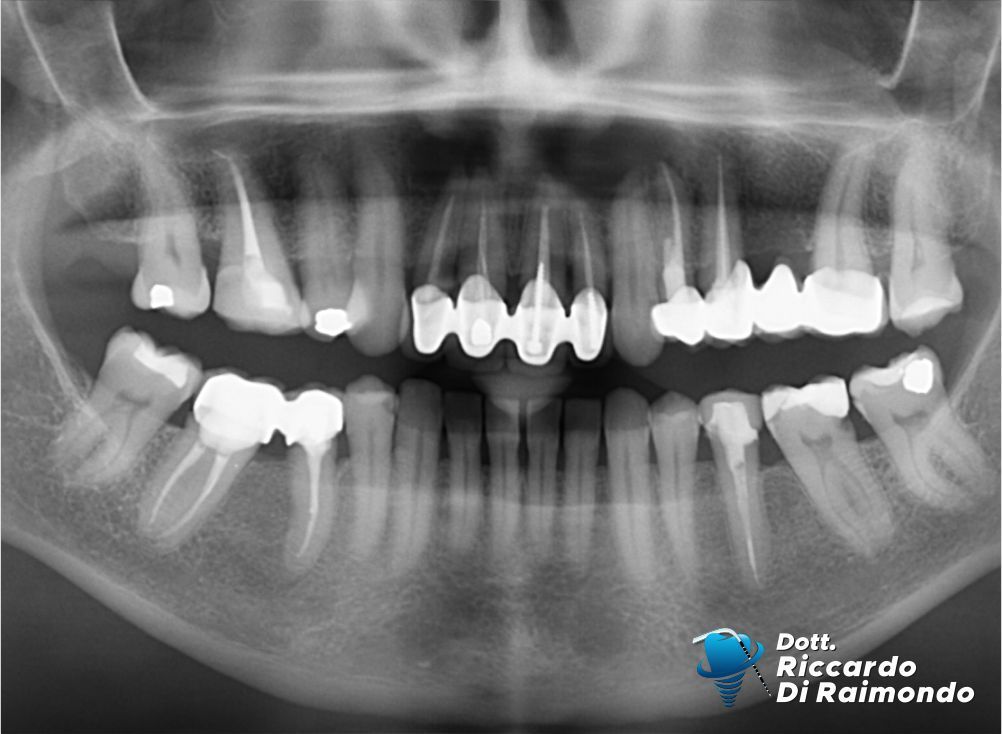

Rimozione cisti mascellare superiore frontale

Fine Trattamento